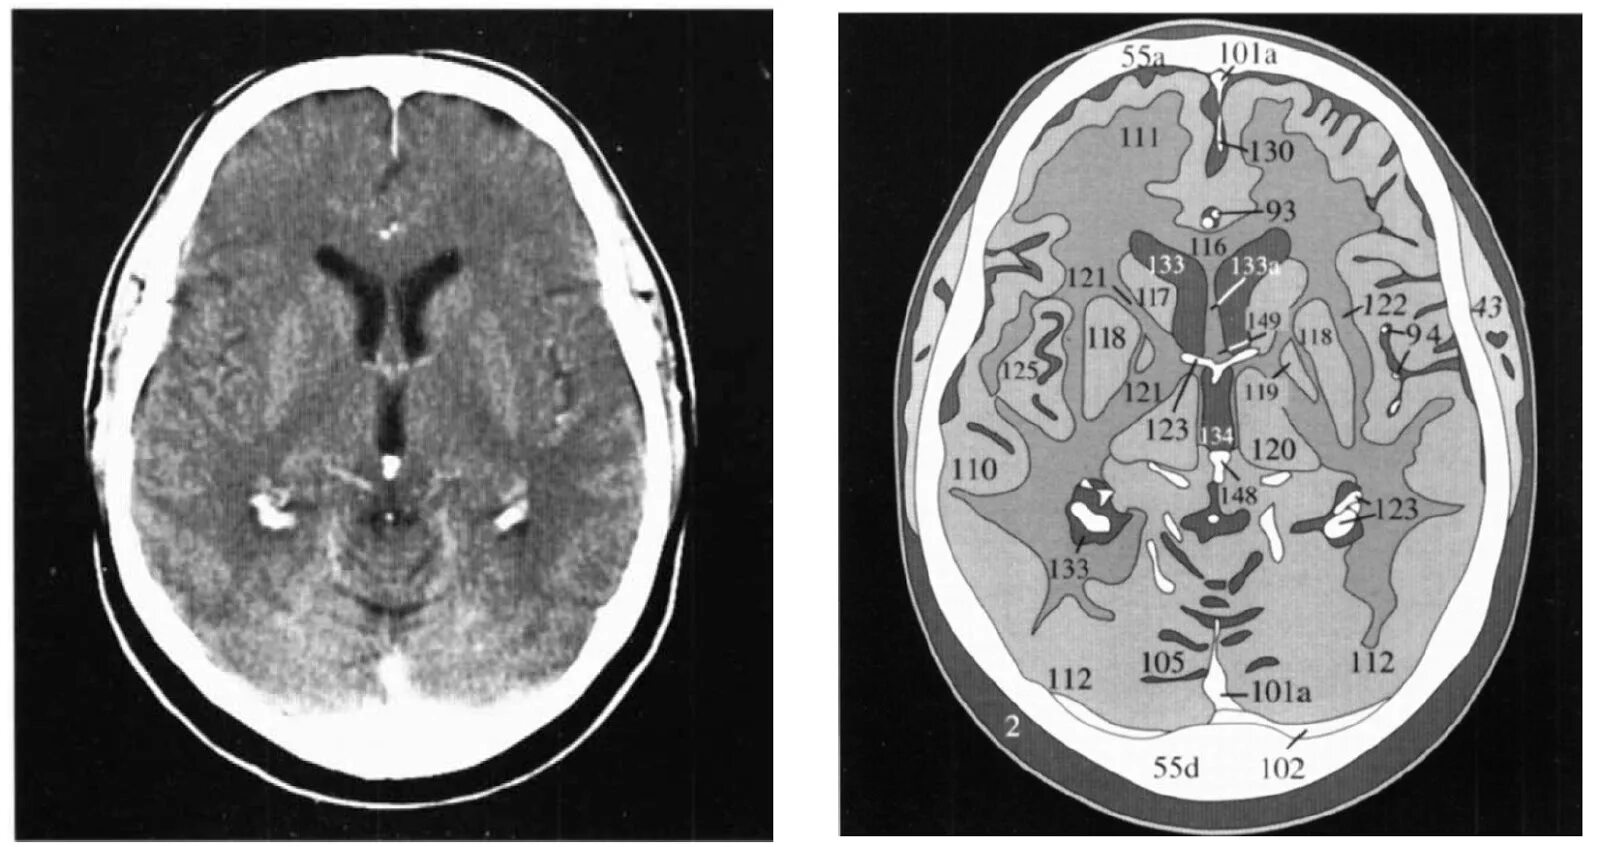

Какие виды кт